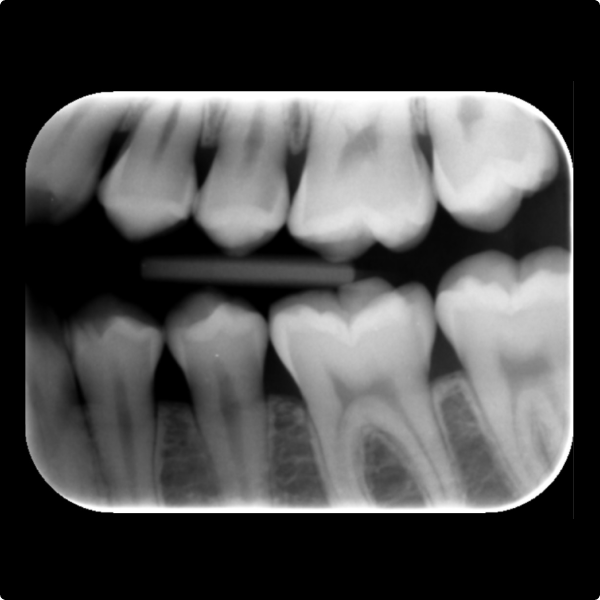

When a 17-year-old patient arrived for a routine six-month check at Dr Kiran Shankla’s practice, there were no complaints or concerns raised by the patient. During the examination a subtle colour change was observed on the upper left premolar. A bite-wing X-ray revealed a cavity, further confirmed with the aid of software.